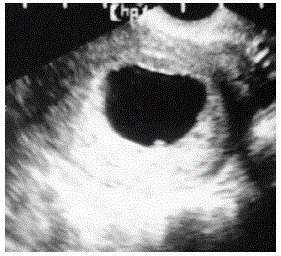

A definição de aborto é expulsão prematura do útero de produtos embrionários da concepção ou de um feto inviável.

Paciente GII PI com 15 semanas de acompanhamento.

Baseado na imagem disponibilizada, qual o seu diagnóstico?